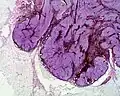

Histologie